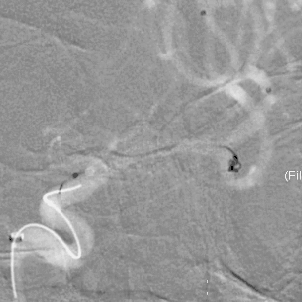

栓塞过程

填塞一枚Jasper®SS弹簧圈,由于瘤囊较小,担心弹簧圈的稳定性,半释放支架后,顺利填入第二枚Jasper®SS弹簧圈。

术后即刻影像